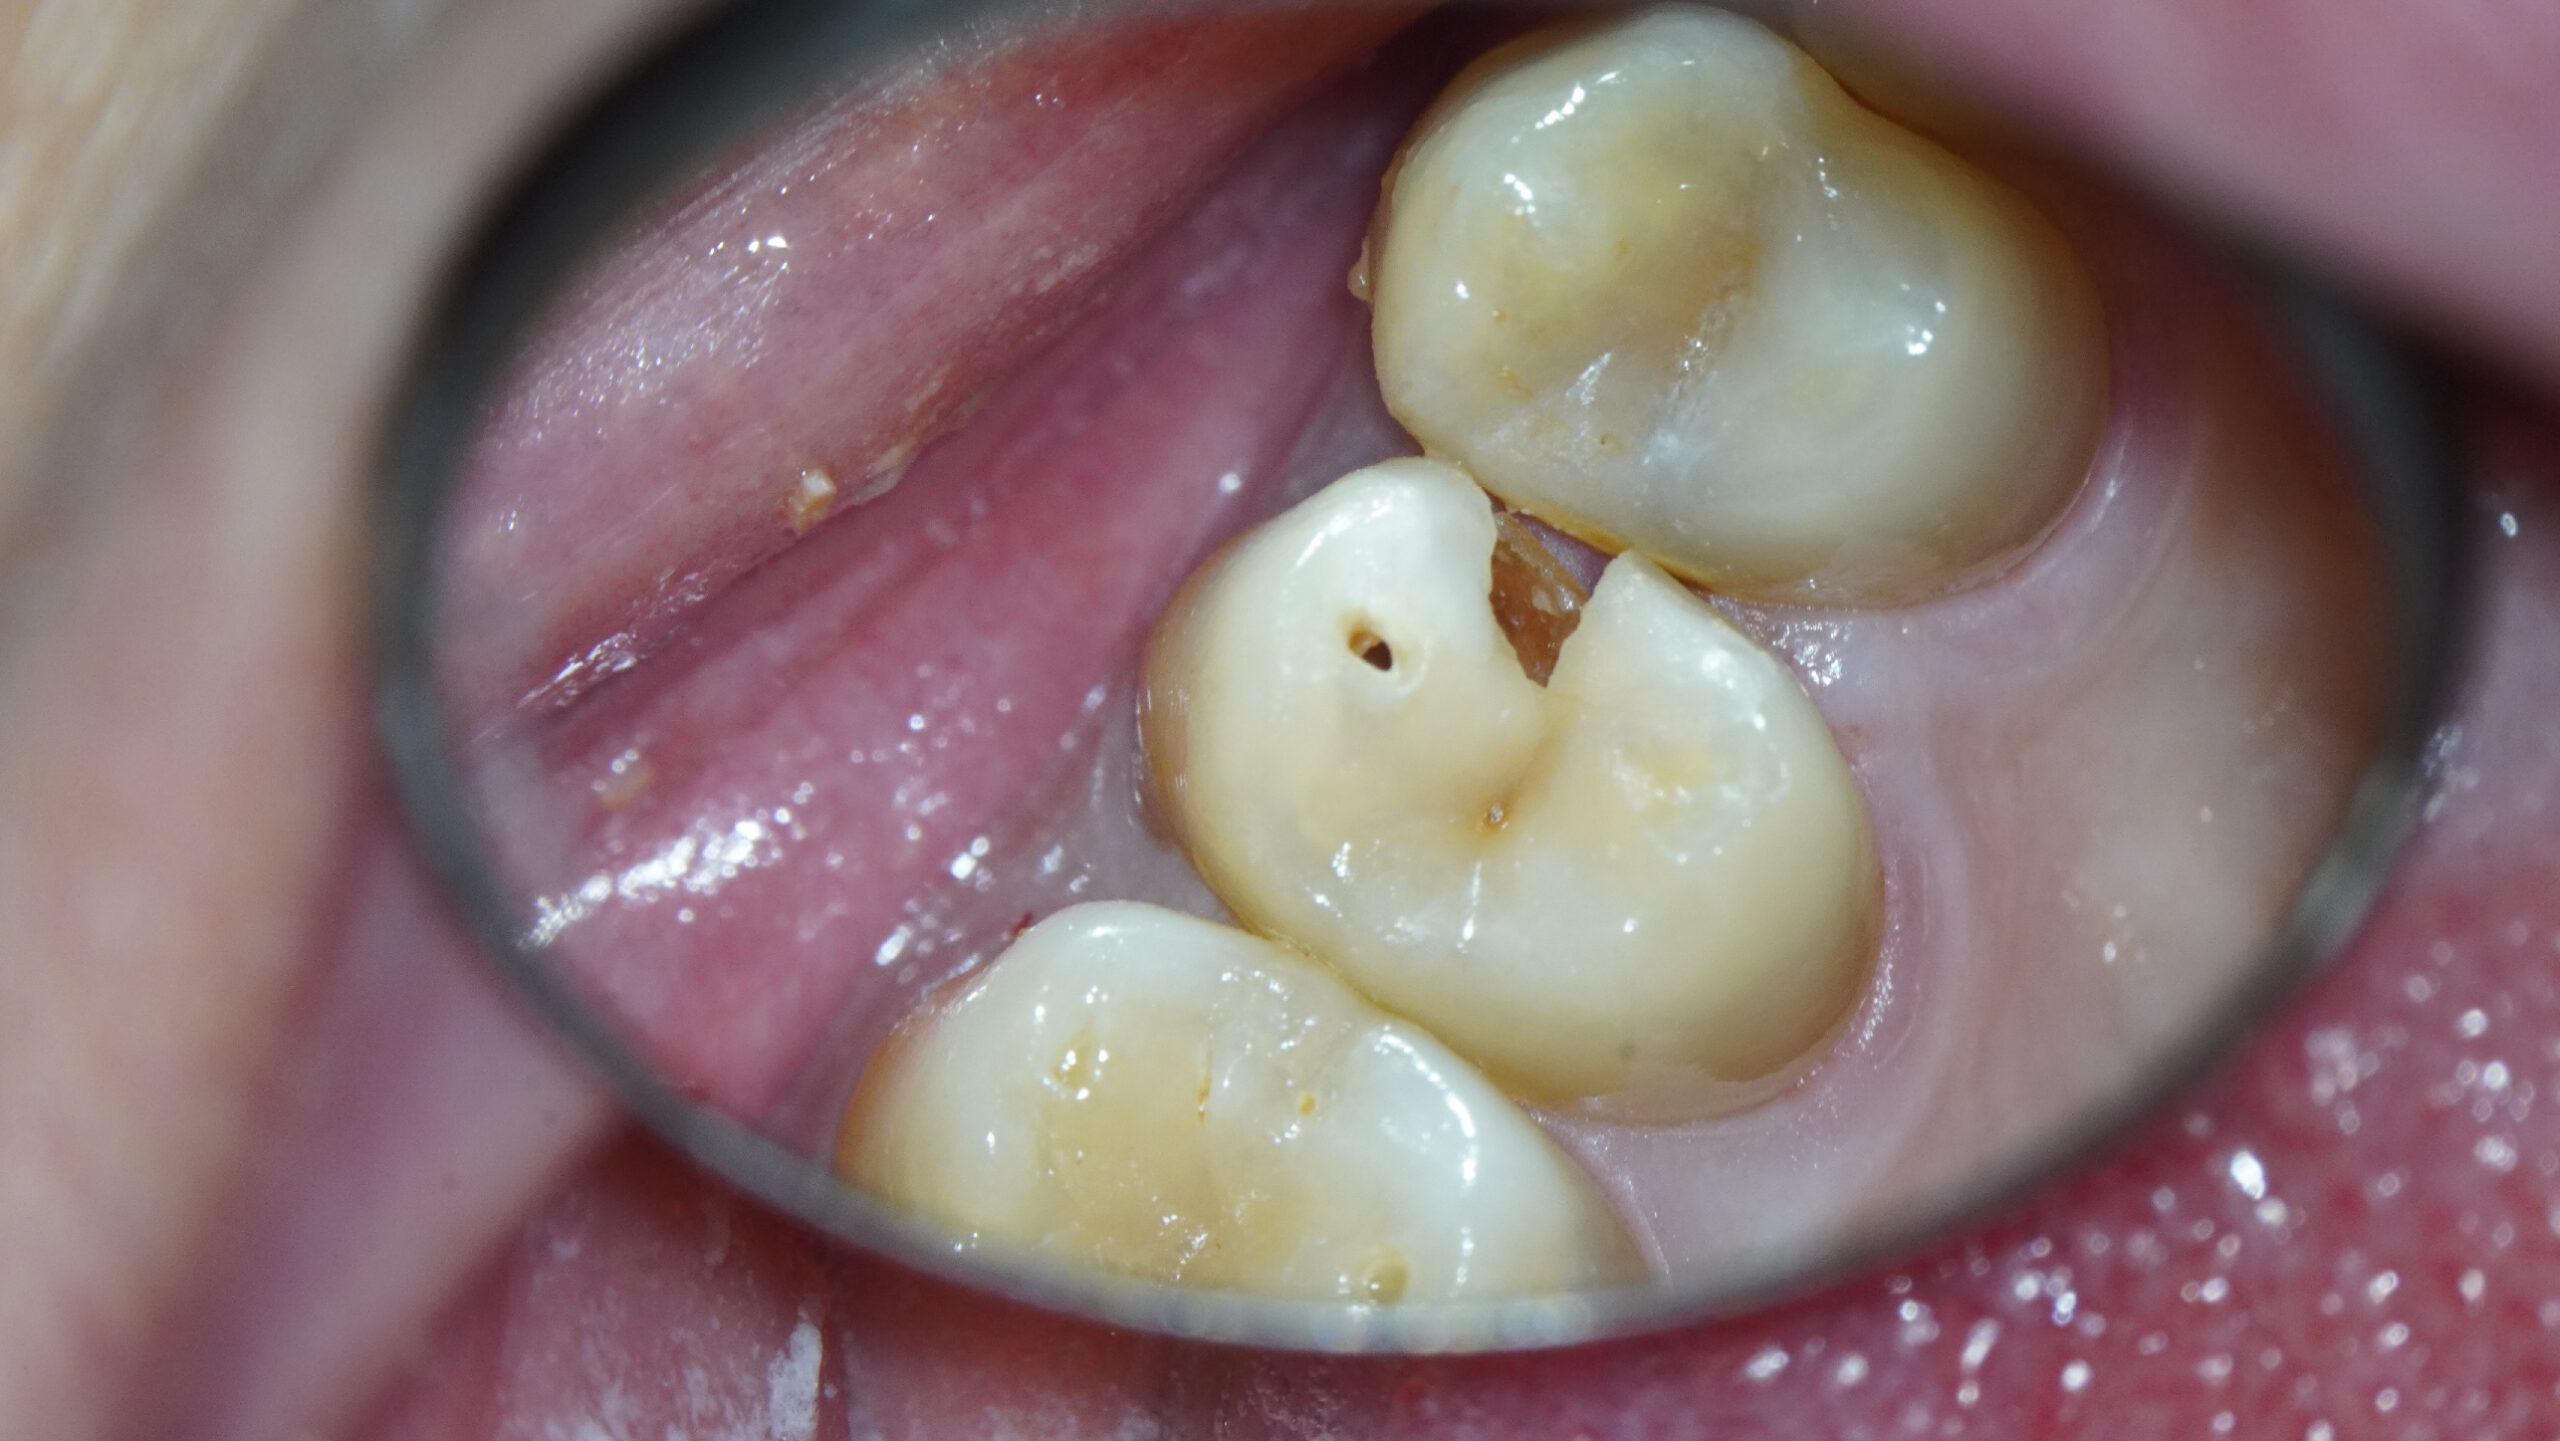

* Haz click sobre las imágenes para verlas a mayor tamaño

Haz click sobre las imágenes para verlas a mayor tamaño y a color